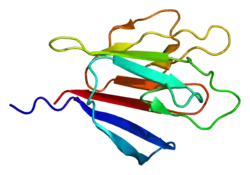

Antigen Kiel 67, also known as Ki-67 or MKI67 (marker of proliferation Kiel 67), is a protein that in humans is encoded by the MKI67 gene (antigen identified by monoclonal antibody Ki-67).[5][6][7]

Antigen KI-67 is a nuclear protein that is associated with cellular proliferation and ribosomal RNA transcription.[7] Inactivation of antigen KI-67 leads to inhibition of ribosomal RNA synthesis,[8] but does not significantly affect cell proliferation in vivo: Ki-67 mutant mice developed normally and cells lacking Ki-67 proliferated efficiently.[9]

The Ki-67 protein (also known as MKI67) is a cellular marker for proliferation,[10] and can be used in immunohistochemistry. It is strictly associated with cell proliferation. During interphase, the Ki-67 antigen can be exclusively detected within the cell nucleus, whereas in mitosis most of the protein is relocated to the surface of the chromosomes.[11] Ki-67 protein is present during all active phases of the cell cycle (G1, S, G2, and mitosis), but is absent in resting (quiescent) cells (G0).[12] Cellular content of Ki-67 protein markedly increases during cell progression through S phase of the cell cycle.[13] In breast cancer Ki67 identifies a high proliferative subset of patients with ER-positive breast cancer who derive greater benefit from adjuvant chemotherapy.[14][15]